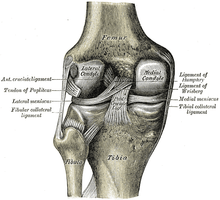

![]() Diagram of the knee | |

The posterior cruciate ligament (or PCL) is one of the four major ligaments of the knee. It connects the posterior intercondylar area of the tibia to the medial condyle of the femur. This configuration allows the PCL to resist forces pushing the tibia posteriorly relative to the femur.

The PCL is located within the knee joint where it stabilizes the articulating bones, particularly the femur and the tibia, during movement. It originates from the lateral edge of the medial femoral condyle and the roof of the intercondyle notch [2] then stretches, at a posterior and lateral angle, toward the posterior of the tibia just below its articular surface.[3][4][5][6]